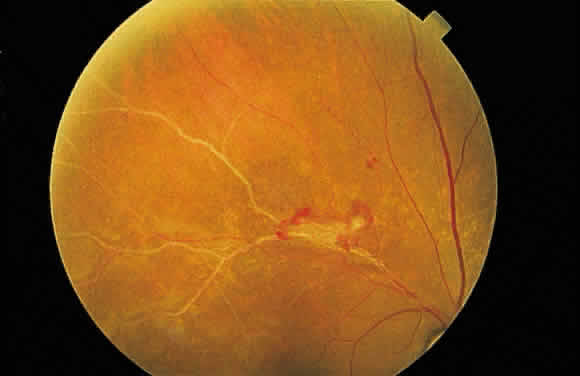

Fig. 13. A. Fundus photograph of a subpigment epithelium hemorrhage superotemporal

to the disc secondary to a macroaneurysm. Notice its dark color and sharp

border. The central portion of the hemorrhage has extended through

the sensory retinal to the subinternal limiting membrane area. B. Fluorescein angiography showing the retinal vessels overlying the deep

hemorrhage but obscured by the central extension anteriorly. (B, courtesy of William Tasman, MD, Philadelphia, PA) Fig. 13. A. Fundus photograph of a subpigment epithelium hemorrhage superotemporal

to the disc secondary to a macroaneurysm. Notice its dark color and sharp

border. The central portion of the hemorrhage has extended through

the sensory retinal to the subinternal limiting membrane area. B. Fluorescein angiography showing the retinal vessels overlying the deep

hemorrhage but obscured by the central extension anteriorly. (B, courtesy of William Tasman, MD, Philadelphia, PA)